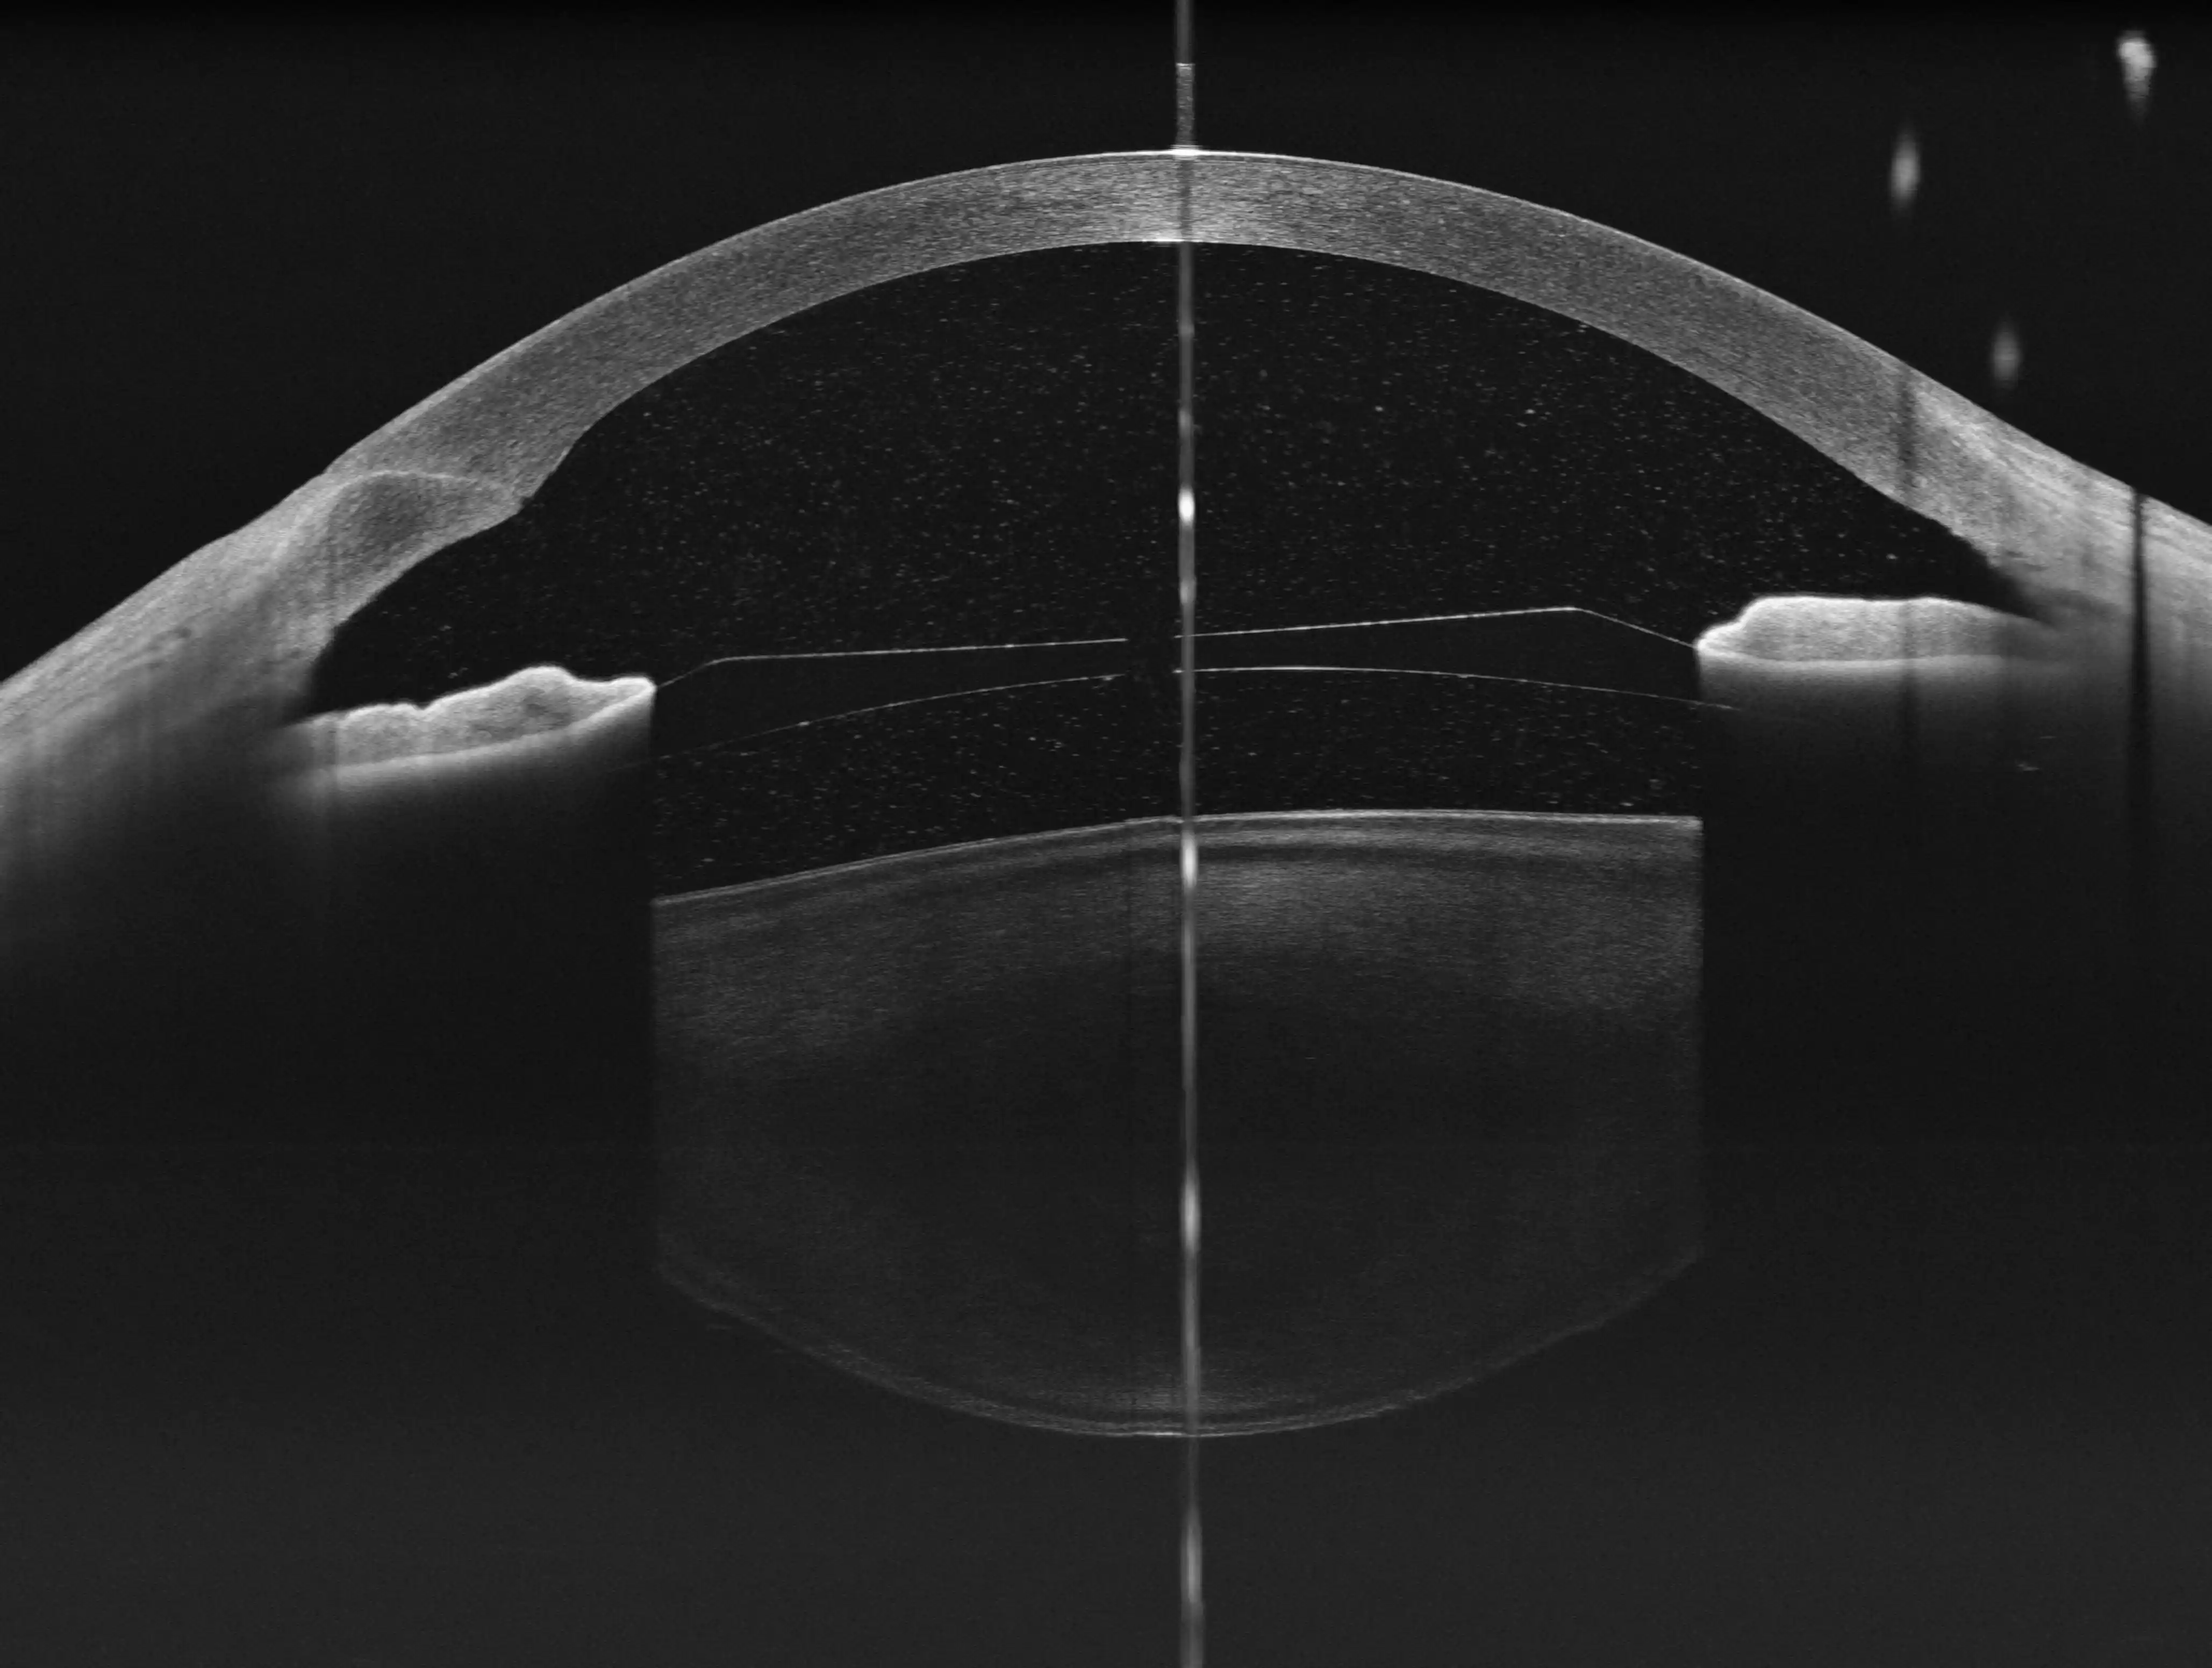

Kompleksowe obrazowanie

Zapewnia pełnozakresowe skany zarówno przedniego (do 24 mm długości i 15 mm głębokości), jak i tylnego (do 17 mm długości i 12 mm głębokości) segmentu oka w jednym urządzeniu, eliminując potrzebę inwestowania w wiele specjalistycznych aparatów.

Obrazowanie wysokiej rozdzielczości

z Full-range Swept Source OCT

Kompleksowa diagnostyka – wszystko w jednym aparacie

Pełne badanie przedniego i tylnegosegmentu

oka w jednym urządzeniu

YAlkaid łączy możliwości SS-OCT do zaawansowanego obrazowania zarówno siatkówki, naczyniówki, jak i struktur przedniego odcinka. Placówka nie musi inwestować w kilka wyspecjalizowanych urządzeń — kompleksowa diagnostyka okulistyczna odbywa się w jednym systemie, co oszczędza miejsce, czas i środki oraz przyspiesza ścieżkę pacjenta.

Głęboka penetracja

Urządzenie zapewnia większą głębokość skanu w tylnym odcinku (12 mm) i przednim odcinku (15 mm), co jest szczególnie korzystne w obrazowaniu ciała szklistego, naczyniówki oraz struktur przedniego odcinka

Optymalny balans

Stanowi idealny wybór do kompleksowego zastosowania OCT w jednym urządzeniu, oferując pełnozakresowe obrazowanie przedniego i tylnego segmentu oka

Analiza Segmentu Przedniego (AS)

Pomiary ilościowe, parametry panoramiczne, mapa grubości rogówki, głębokość komory przedniej i kąt przesączania